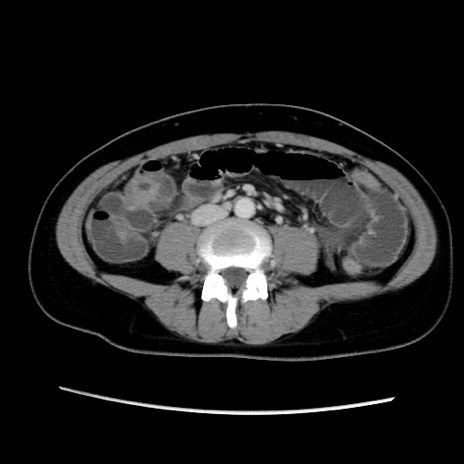

症例39(横断像)

【症例】40歳代女性

【主訴】上下腹部痛

【現病歴】2日目から下腹部痛あり。夜間は痛みで眠れなかった。昨日より上腹部痛と下痢が出現。臥位で痛みは軽快したため、休んでいた。本日になって臥位でも立位でも痛みが強くなってきたため救急要請。

【既往歴】子宮内膜症

【身体所見】部:平坦・軟、左上下腹部に圧痛あり、反跳痛あり。

【データ】WBC 21800、CRP 26.78